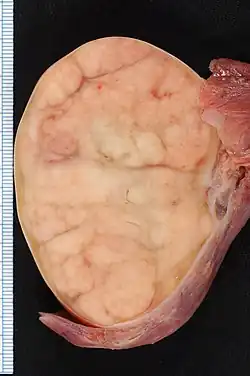

7.4 × 5.5-cm seminoma in a radical orchiectomy specimen.